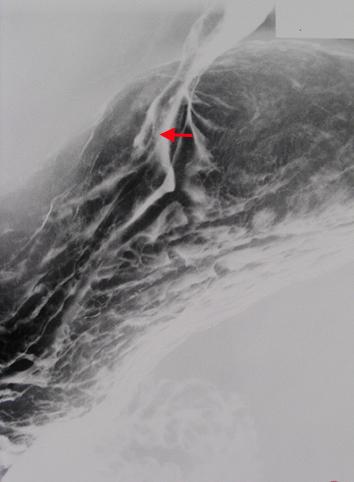

질환(병리주체)의 분류 염증성 및 궤양성질환/위궤양

부위(장기별) 위(부위)/분문

검사방법 X-P

종양의 육안분류 0형(표재형)/IIa형(IIa)

종양의 최대경(밀리미터) 10~14

종양의 심달도 sm